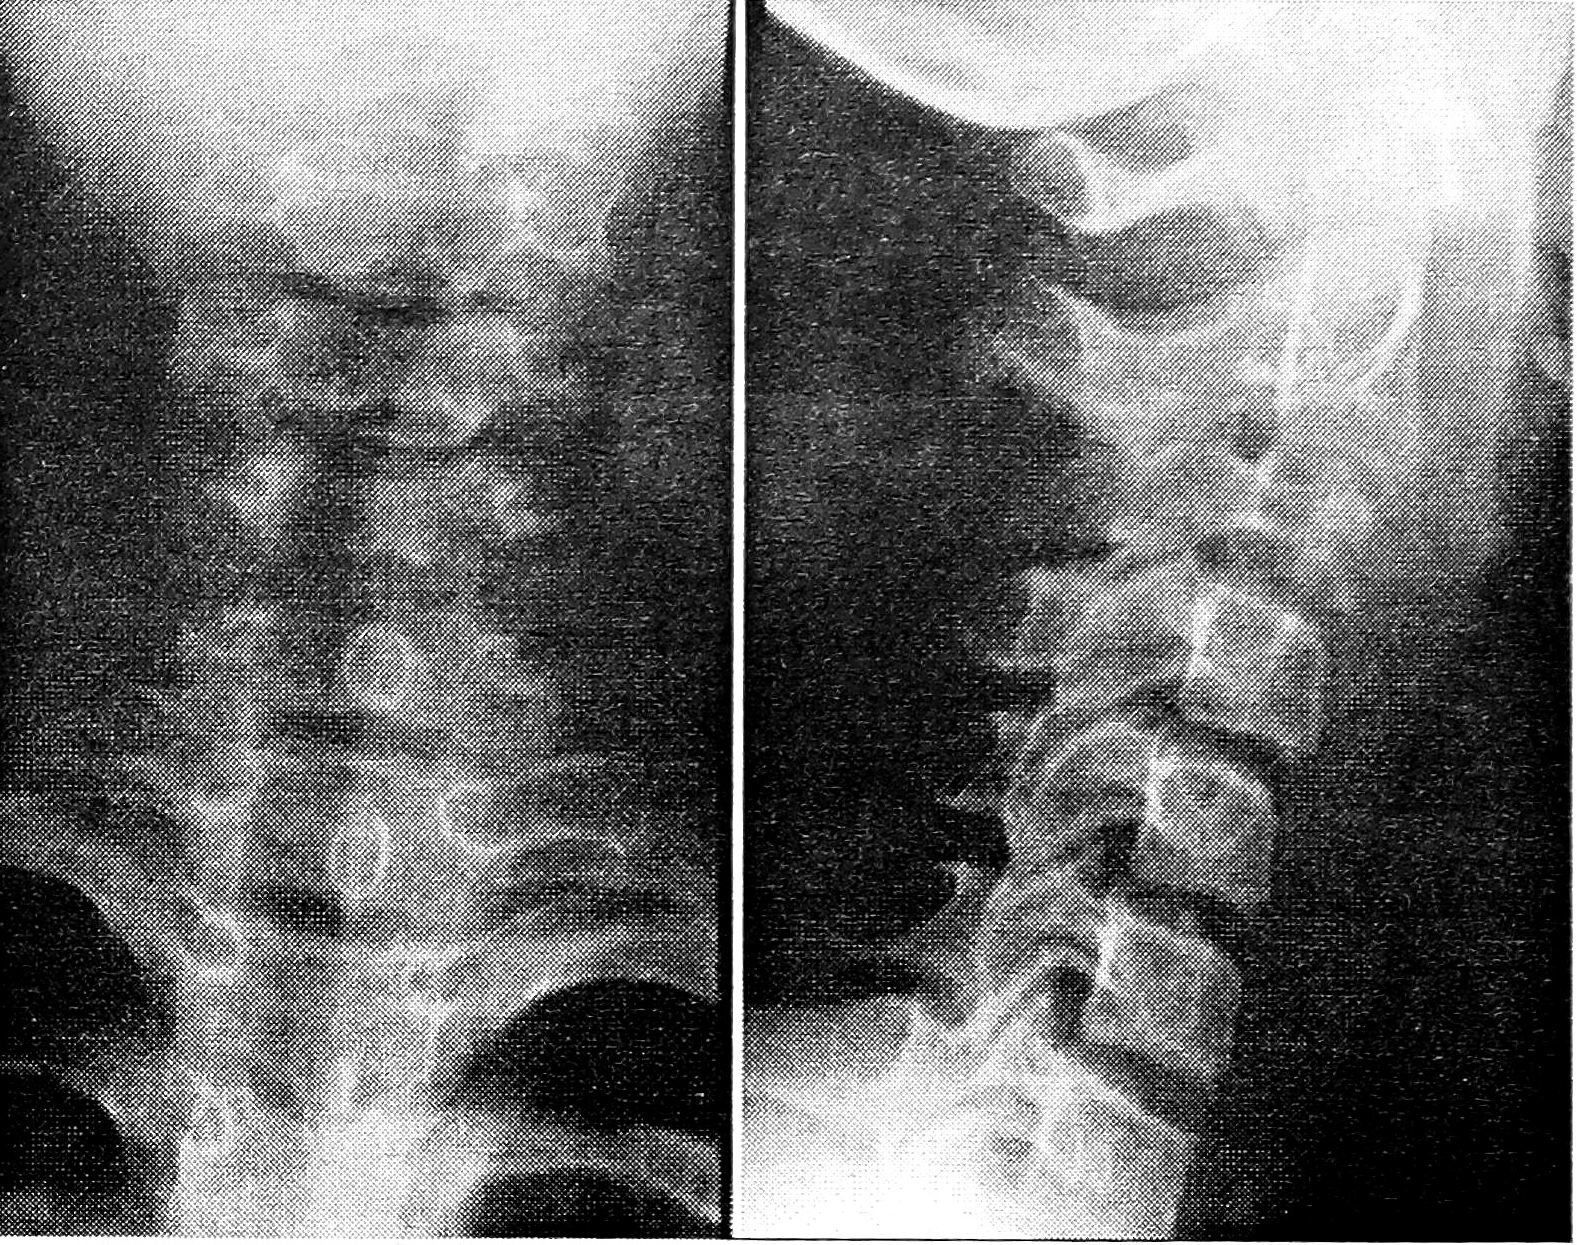

Для АКК характерна фазность течения. Литическая фаза отличалась агрессивностью распространения процесса на смежные структуры позвоночника (рис. 2 на вклейке), фаза репарации — снижением активности, появлением ячеистости, понижением прозрачности очага (рис. 3 на вклейке). Наряду с остеолитической деструкцией ведущим симптомом АКК является выраженное вздутие коркового слоя. В отдельных случаях в результате вздутия нарушается статика, происходит смещение вышележащих позвонков. Частое осложнение АКК — патологический перелом [12]. У 10 детей были поражены два, у 4 — три позвонка и более.

Рис. 2. Больная 11 лет с аневризмальной кистой кости С3 позвонка.

Рентгенограммы: остеолитический очаг деструкции тела и дуги позвонка с экстравертебральным компонентом.